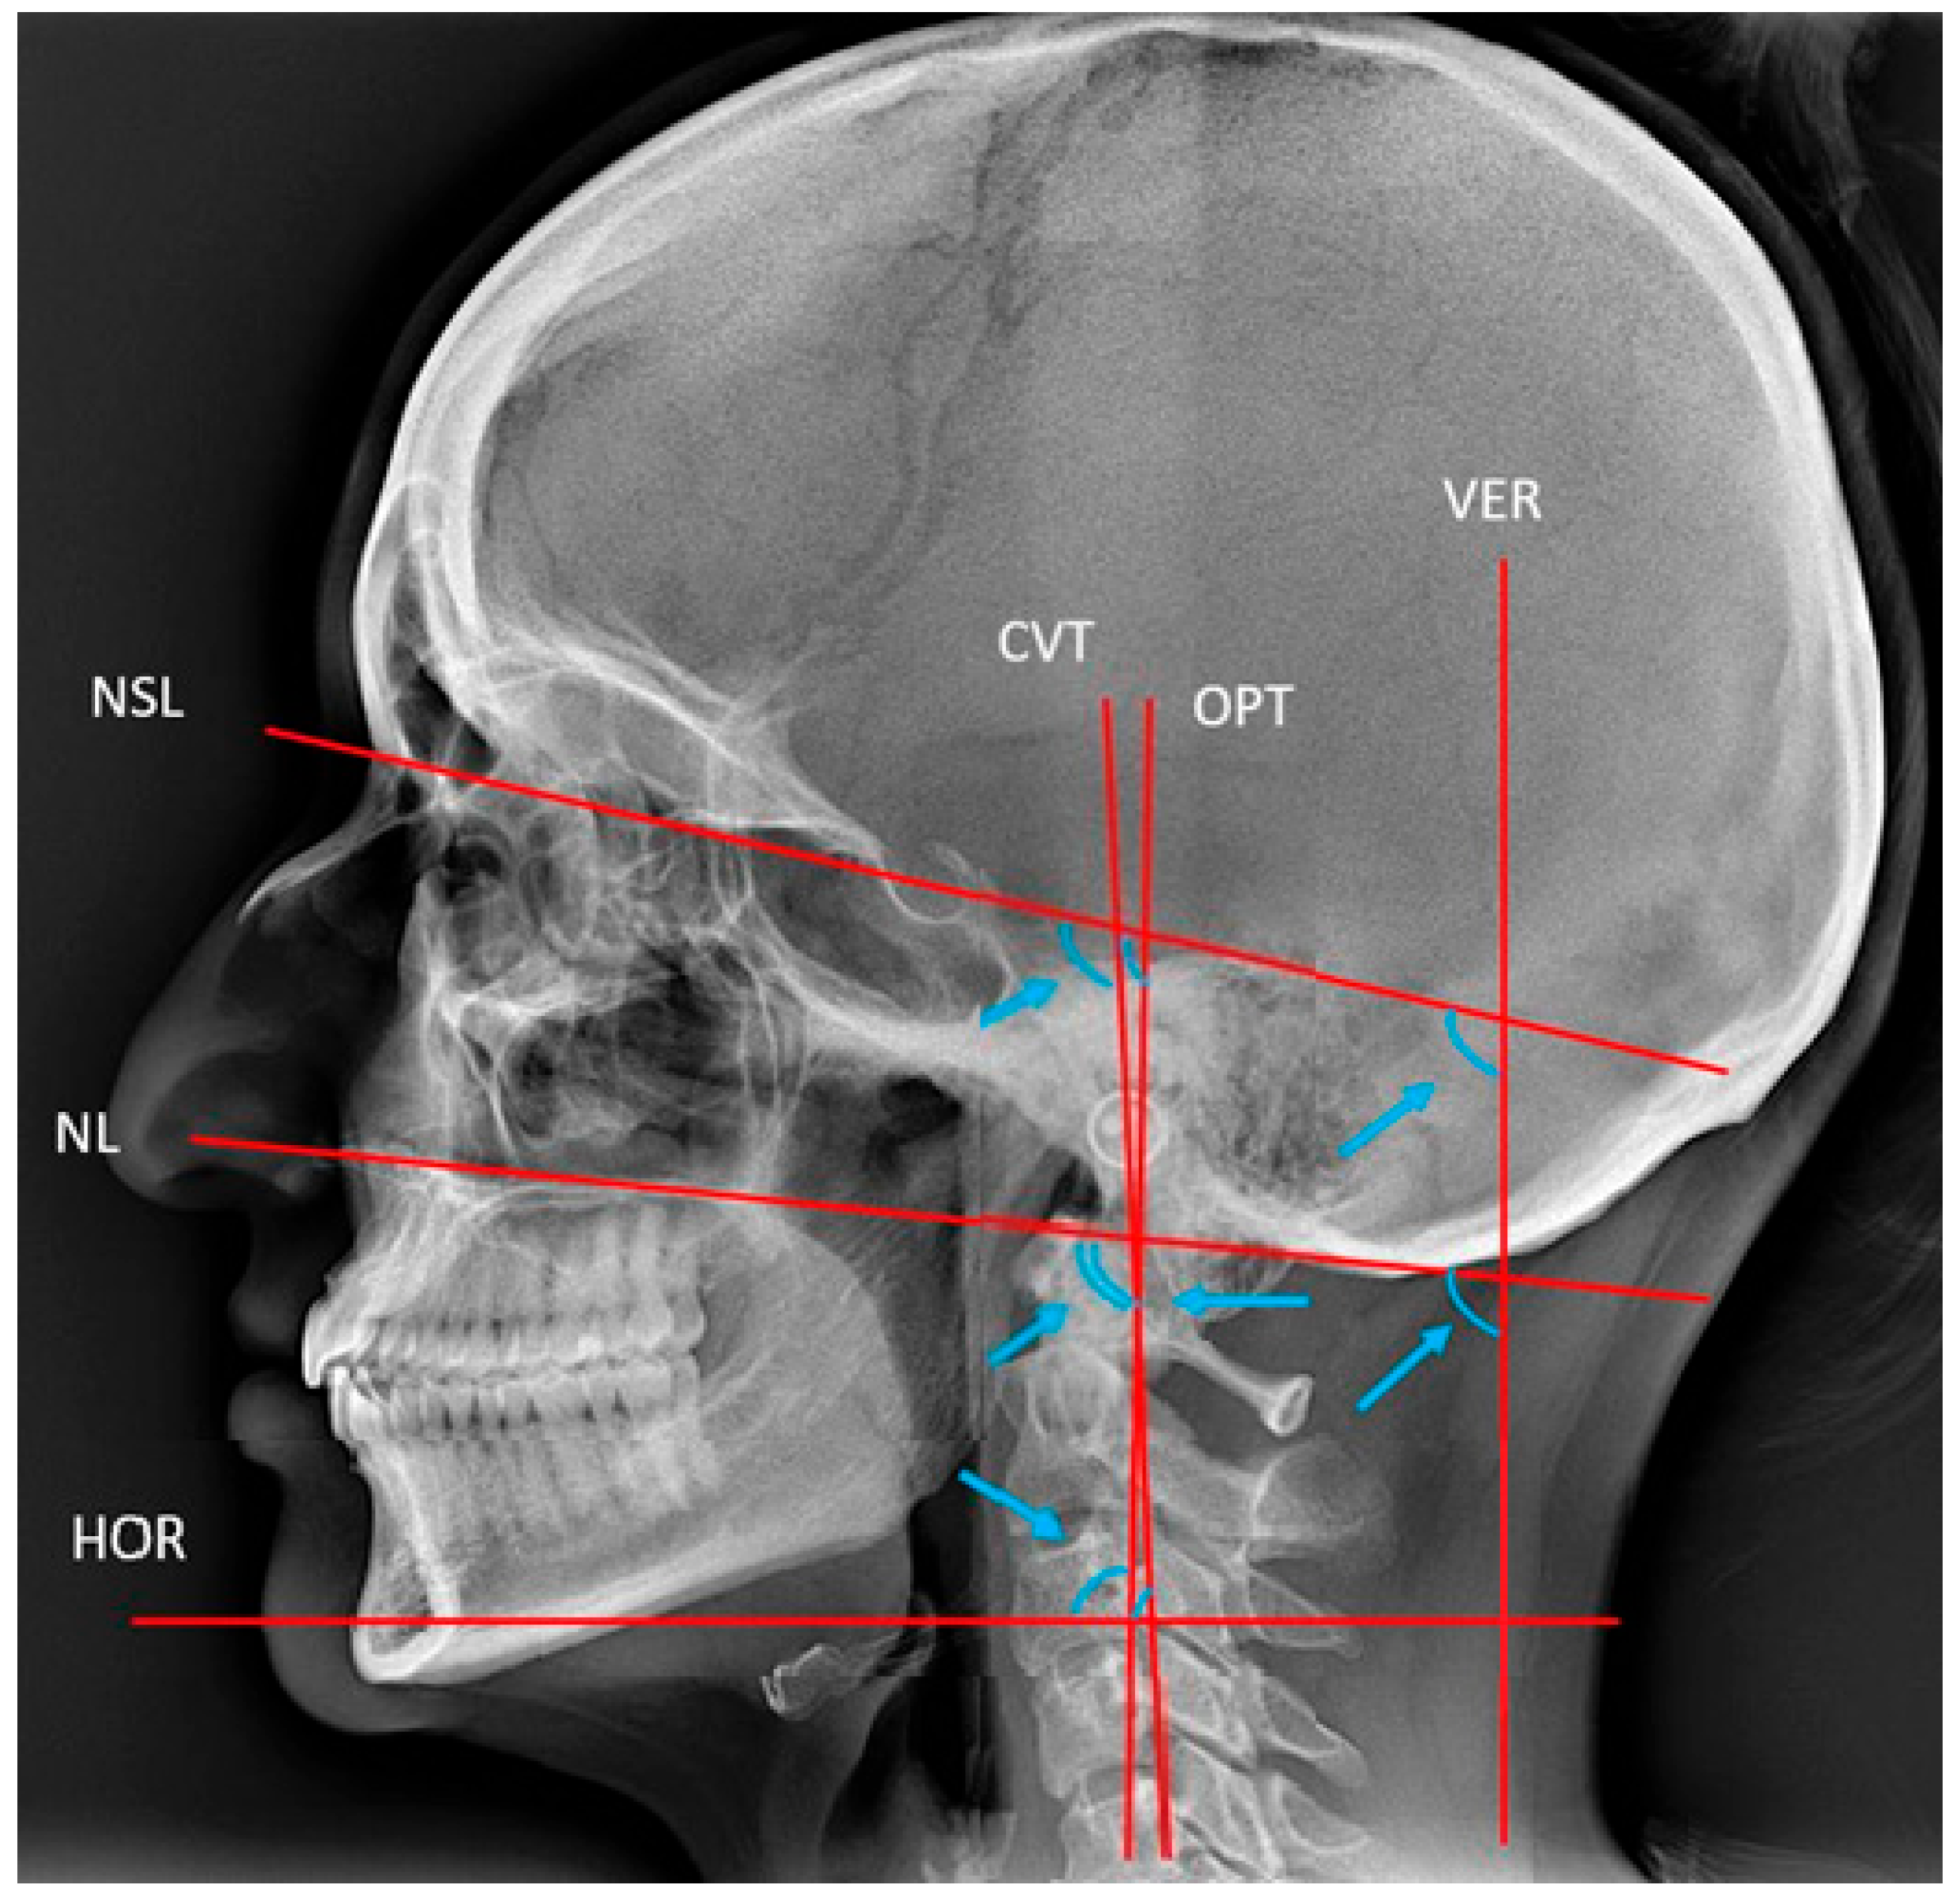

2.2.1. Cephalometric Analysis of Lateral Cephalograms

| Cranio-vertical | |||||||||||

| NSL/VER | 74 | 85.10 | 109.1 | 98.2 | 4.71 | 51 | 87.0 | 115.4 | 99.16 | 6.09 | 0.391 |

| NL/VER | 74 | 83.20 | 102.2 | 92.23 | 4.62 | 51 | 83.2 | 105.7 | 93.54 | 5.37 | 0.468 |

| Cranio-cervical | |||||||||||

| NSL/OPT | 74 | 78.40 | 111 | 94.40 | 6.9 | 51 | 85.8 | 114.9 | 100.86 | 8.26 | ˂0.001 ***b |

| NSL/CVT | 64 | 85.2 | 114.1 | 100.72 | 6.23 | 47 | 92 | 121 | 106.79 | 8.05 | ˂0.001 ***ab |

| NL/OPT | 74 | 75.8 | 106.1 | 88.53 | 6.73 | 51 | 81.7 | 110 | 95.24 | 7.36 | ˂0.001 ***b |

| NL/CVT | 64 | 83.3 | 107.2 | 94.44 | 6.02 | 47 | 87.3 | 116 | 100.90 | 7.23 | ˂0.001 ***b |

| Cervico-horisontal | |||||||||||

| OPT/HOR | 74 | 75.5 | 107.3 | 94.04 | 6.5 | 51 | 74.8 | 98.3 | 88.33 | 6.05 | ˂0.001 ***b |

| CVT/HOR | 64 | 74.4 | 102.7 | 87.63 | 6.08 | 47 | 71.4 | 94.4 | 82.57 | 5.56 | 0.001 *** |

| Cervical curvature | |||||||||||

| CVT/OPT | 64 | −0.5 | 12.8 | 6.37 | 2.65 | 47 | −2.4 | 12.5 | 5.4 | 2.73 | 0.498 |